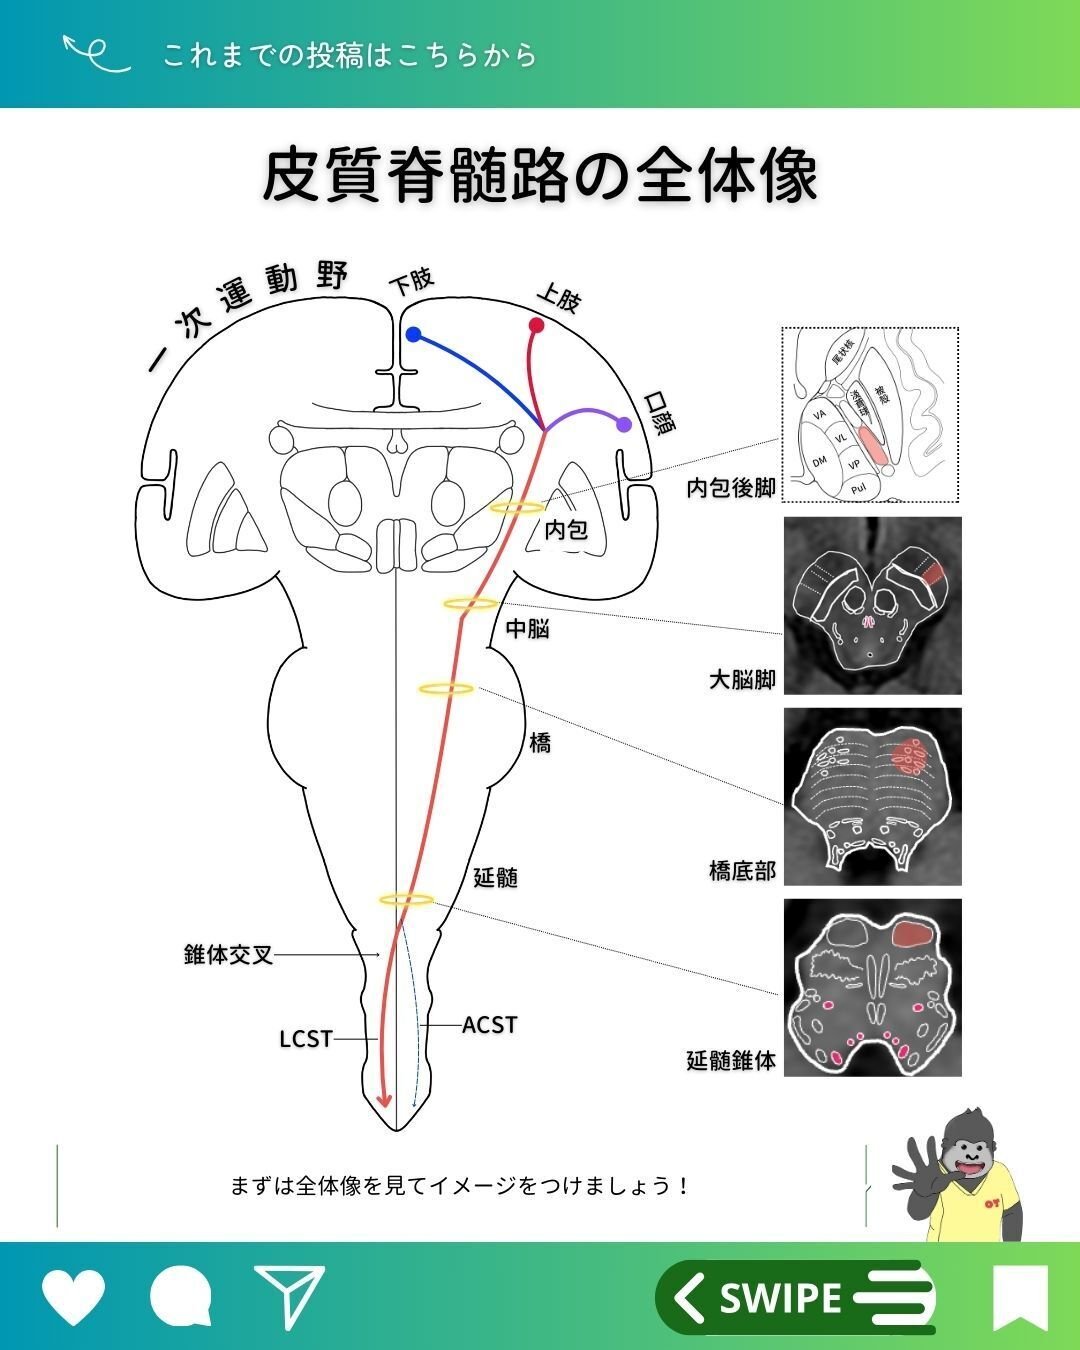

CSTの全体像

まずは全体像を見ていきましょう👀

青:CRST

オレンジ:CST

これらの視点を持つことで、よりイメージがしやすいのではないでしょうか😉?

さらに詳しく見ていくと、下図のようなポイントを通過していきます🏃♀️

CSTの代表的な通過ポイント

・一次運動野(6野や3.1.2野からの出力もあります)

・半卵円中心

・放線冠

・内包後脚

・大脳脚(中脳)

・橋

・延髄(錐体交叉)